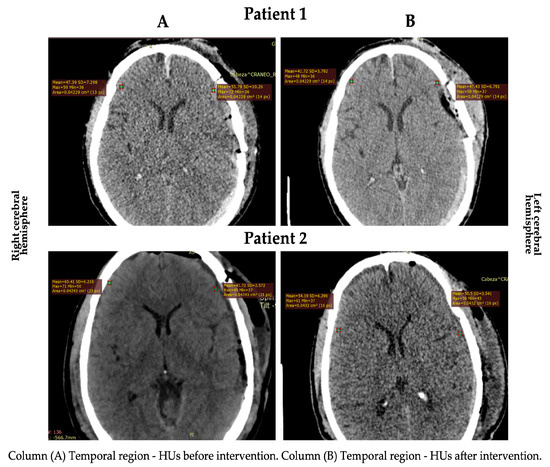

| Before | After | Difference (%) | |

|---|---|---|---|

| RCH | |||

| TR (HU) | |||

| Patient 1 | 47.39 | 41.72 | 05.67 (↓ 11.96) |

| Patient 2 | 65.41 | 54.19 | 11.22 (↓ 17.15) |

| LCH | |||

| Patient 1 | 55.79 | 47.43 | 08.36 (↓ 14.98) |

| Patient 2 | 41.72 | 50.50 | 08.78 (↑ 17.38) |